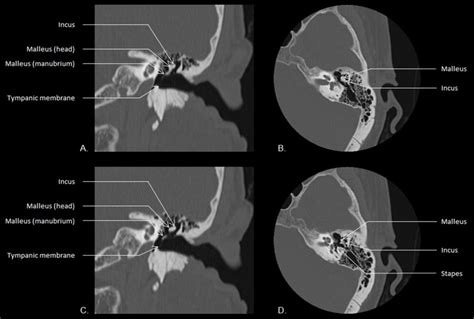

External ear anatomy: The pinna (A), the external acoustic ...

External ear anatomy: The pinna (A), the external acoustic ... from www.researchgate.net